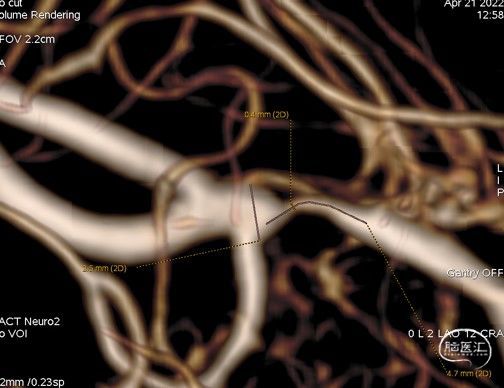

三维重建显示右侧大脑中动脉分叉前部重度狭窄,狭窄段直径0.4mm,狭窄程度约84%: